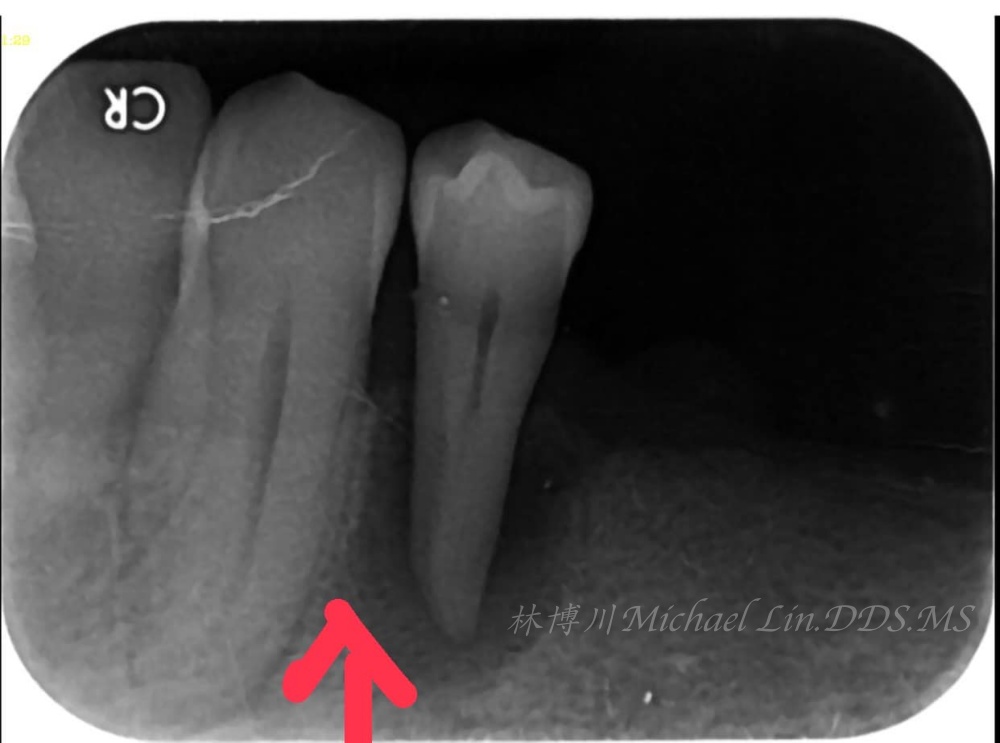

上過我植牙班的學員,在講到 Immediate Implant Placement 即拔即種這個章節時

下一秒就發現這不就跟臨床上「即拔即種」的定位點一模一樣!立刻想把這發現拍下來,回台灣演講時,可分享給學員。

而這張冒險拍到的照片,也提供醫師做植牙時,Immediate Implant Placement一個很好的聯想工具。